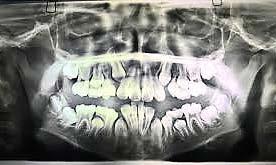

a. Observar radiográficamente las características anatómicas y dimensionales de los caninos superiores e inferiores respecto a dientes adyacentes (Figura 11).

b. Identificar radiográficamente la posición en que se encuentra el canino, respecto a los dientes adyacentes (Figura 12).

c. Determinar que angulación y posición existe entre el eje longitudinal

del canino respecto al plano oclusal, donde “V” es vertical, “M” es mesioangular, “H” es mesiohorizontal, “MI” vertical invertido, “D” distohorizontal (Figura 13).

A partir de los 8 años, se puede observar radiográficamente el inicio de la reabsorción del canino deciduo (Figura 17).

El seguimiento del trayecto canino con un estudio radiográfico postero anterior, lateral de cráneo y ortopantomográfico, a partir de la edad señalada anteriormente, también es una herramienta efectiva que permite obtener un diagnóstico inicial, donde podrá observarse si se ha iniciado la reabsorción radicular del canino deciduo e identificar qué

dirección o trayecto está tomando el canino permanente (Figura 18).

Ubicación del canino

Un método sencillo para obtener el diagnóstico de inclusión canina en proceso o declarada, cuando no se realizó un seguimiento desde una edad temprana, será utilizando como herramienta de diagnóstico inicial, una ortopantomografia, donde al trazar puntos, planos y líneas de referencia en estructuras dentocraneales y en el eje longitudinal del canino propiamente, podremos ubicar tridimensionalmente el sitio de inclusión en proceso de formación radicular (estadio del 6 al 9), o definitivo, cuando el ápice se ha cerrado (estadio 10 de Nolla) y el diente no erupcionó8 (Figura 20).

Así lo mencionan (Ericson y Kurol) (Etal Eur J Orthod. 1988; 10:283–95)4, en el que proponen una clasificación, utilizando como herramienta una ortopantomografía y la angulación del canino, usando planos, líneas de referencia y la determinación de sectores, ubicando a estos de la siguiente manera: